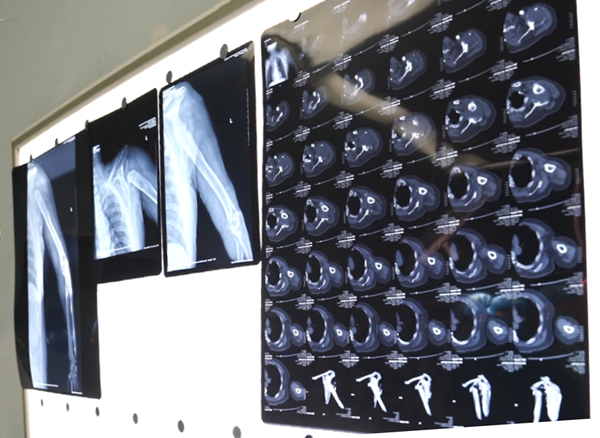

△患者術(shù)前CT影像

蘭先生住院后,為其完善X線及CT檢查發(fā)現(xiàn),由于患者左臂肱骨頭缺失,左側(cè)肩胛盂唇結(jié)構(gòu)破壞缺失,肱骨與肩胛骨的長期磨損造成了骨頭大量缺失,關(guān)節(jié)周圍的肌肉韌帶攣縮變短,利用傳統(tǒng)治療技術(shù),無法徹底解決患者的問題。為了尋求且制定最佳的治療方案,張浩沙強(qiáng)將蘭先生的情況向王志剛匯報。王志剛30余年專研關(guān)節(jié)疾病的診治,具有極其豐富的治療經(jīng)驗(yàn),在關(guān)節(jié)外科業(yè)內(nèi)是享譽(yù)疆內(nèi)外的知名專家。他全面了解了蘭先生的病情后,反復(fù)思量與琢磨,決定依靠3D打印技術(shù),為患者進(jìn)行定制肩關(guān)節(jié)假體反肩置換手術(shù),既能重建肩關(guān)節(jié)穩(wěn)定性,還能重建肩關(guān)節(jié)功能,提高患者生活質(zhì)量。